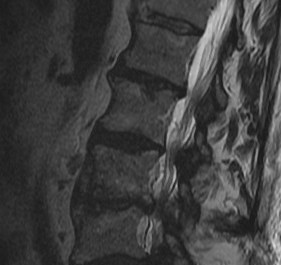

MRI

Disc

Normal disc / bright T2 signal

Degenerative disc / dark T2

Modic End Plate Changes

Classification of bone marrow changes in bone marrow adjacent to vertebral end plates

Type 1: High on T2 / Low on T1

Type 2: High on T2 / High on T1 (lipid changes)

Type 3: Low on T2 and T1 (sclerotic)